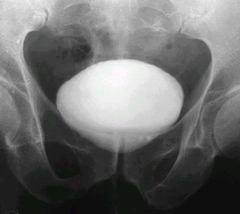

引起膀胱結(jié)石的直接原因是哪些?患者咨詢:專家你好,我得了膀胱結(jié)石。醫(yī)生說導(dǎo)致這個疾病的原因比較復(fù)雜,我現(xiàn)在就是想要了解下導(dǎo)致這個疾病的直接原因是哪些?麻煩專家大概幫我介紹一下吧。

2、關(guān)于膀胱結(jié)石的主要原因之一就是前列腺肥大、膀胱頸狹窄、尿道狹窄等原因會導(dǎo) 致泌尿阻塞,引發(fā)結(jié)石。

4、還有一些原因就是泌尿系統(tǒng)的問題,比如尿道結(jié)石掉下來也會引發(fā)膀胱結(jié)石。